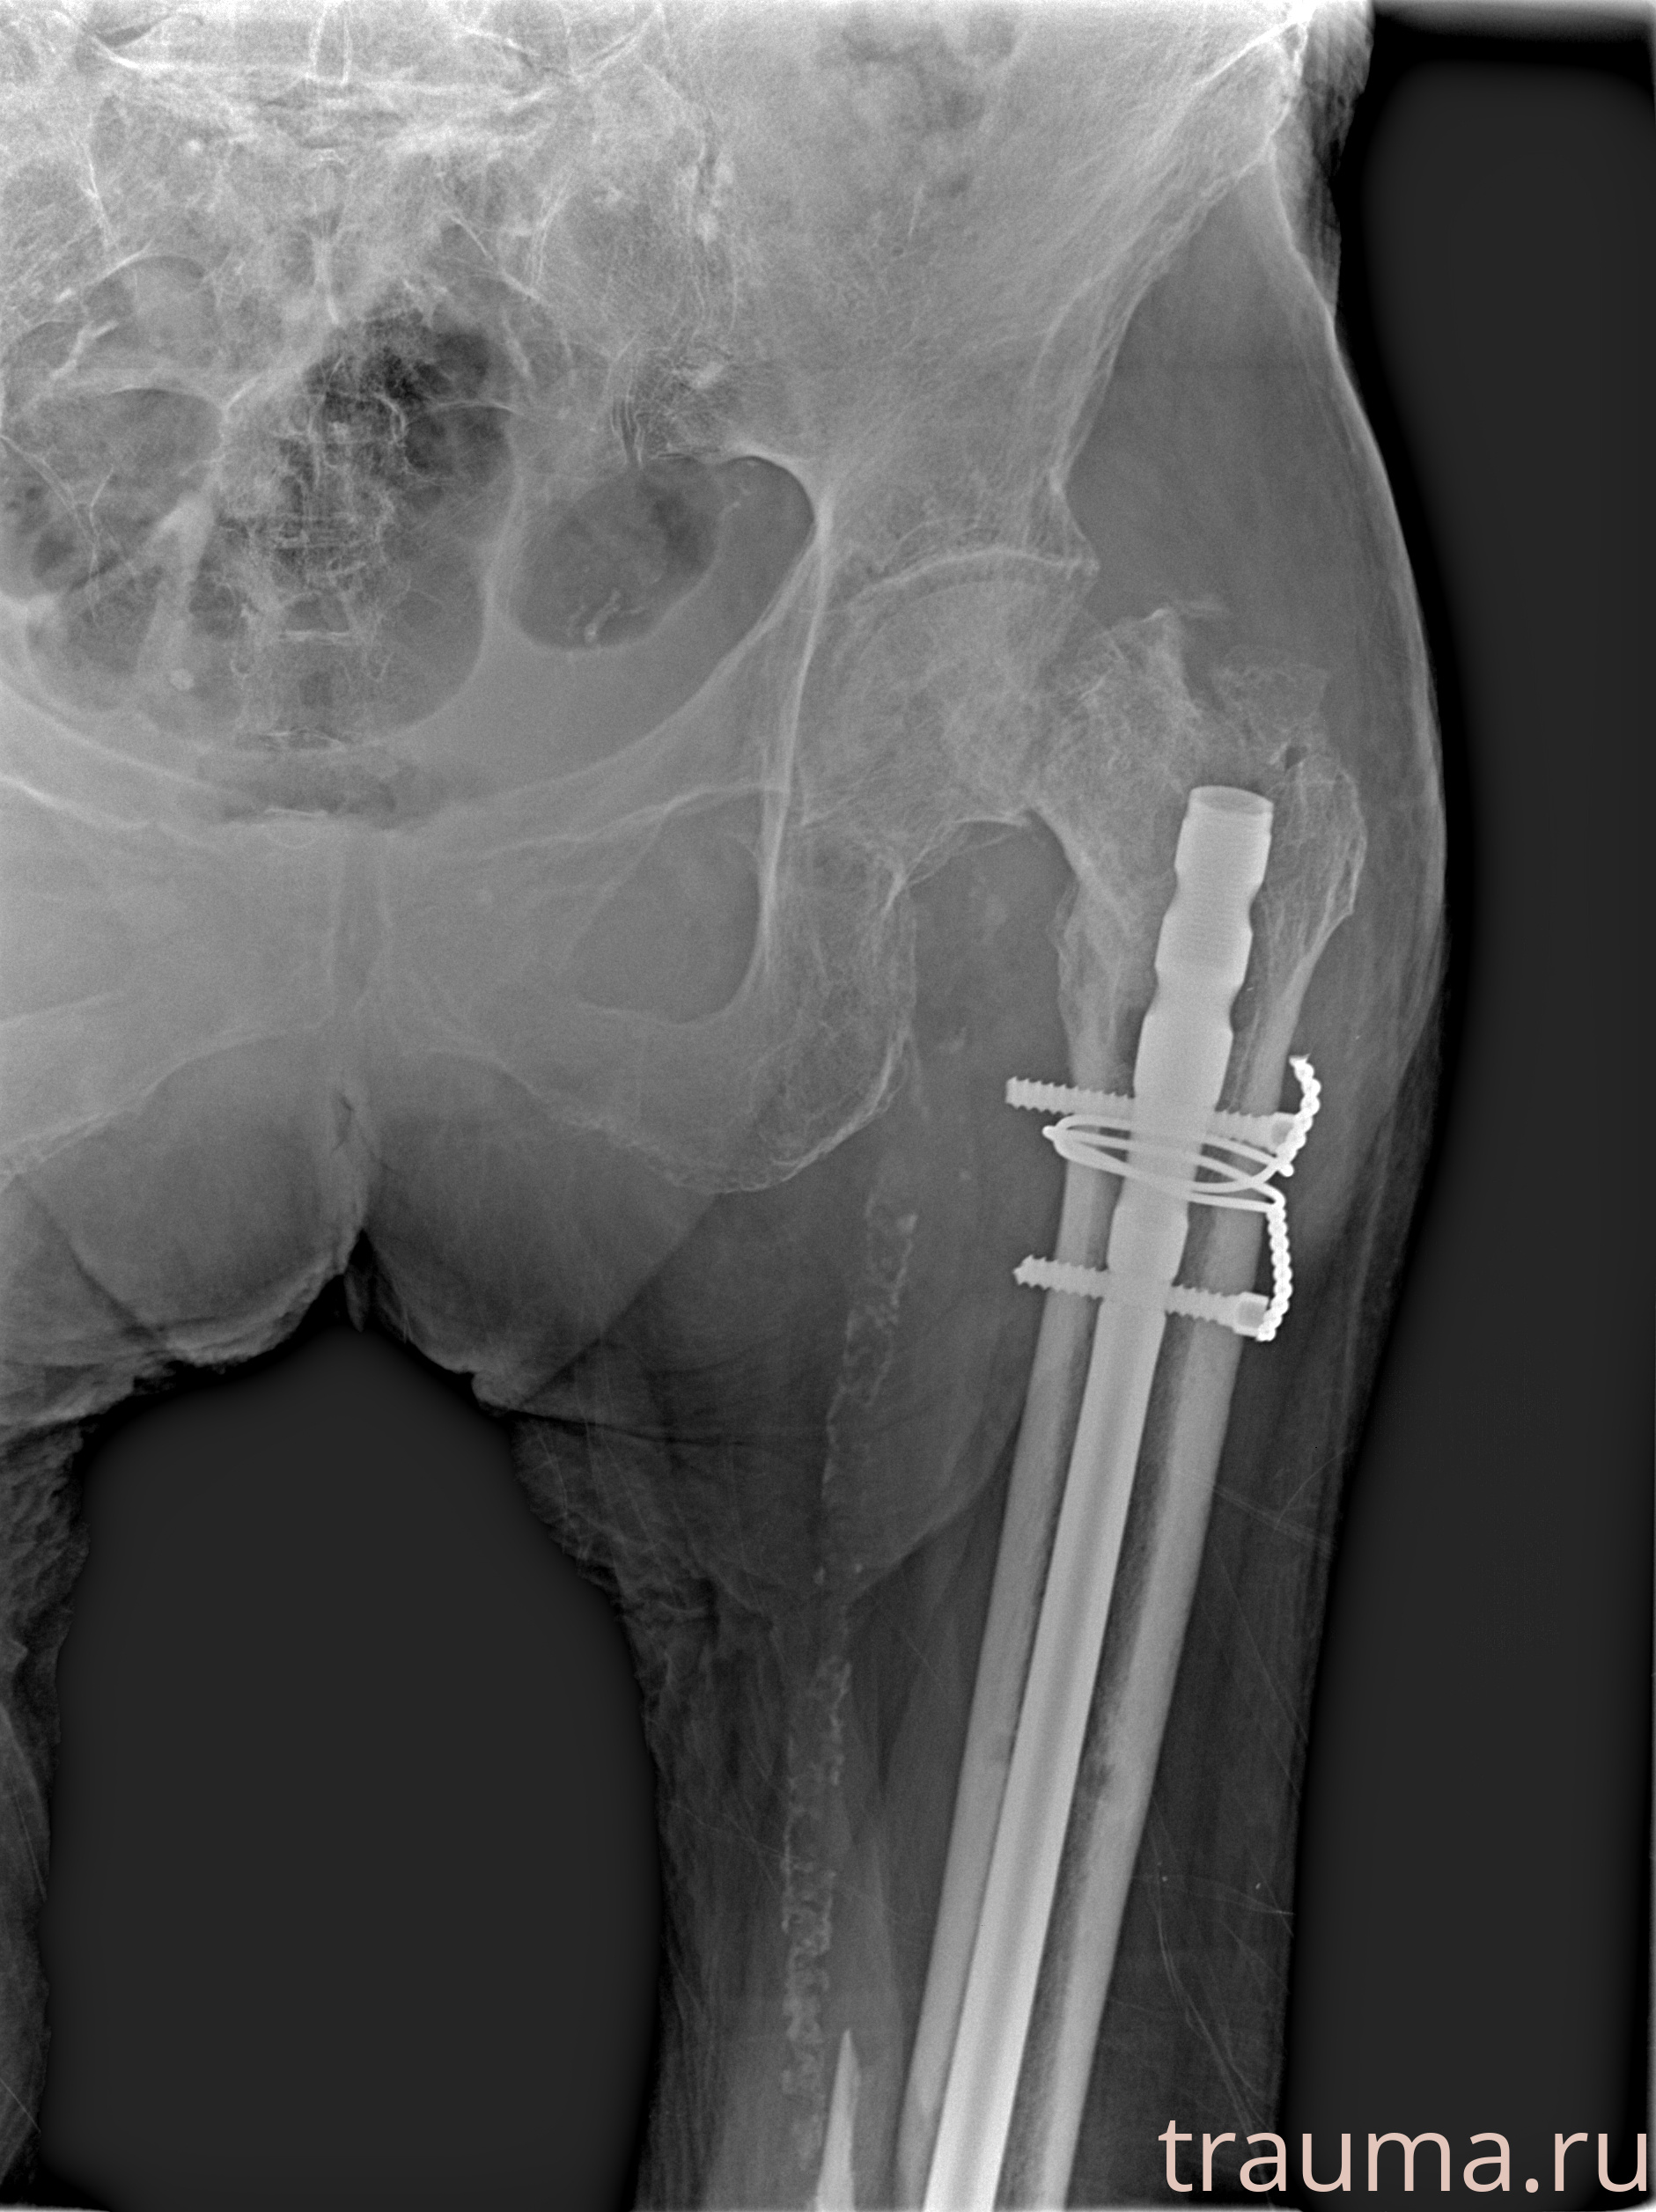

Рентгенограммы

Рентген на дому: по вашему адресу приезжает врач-рентгенолог, травматолог-ортопед с мобильным рентгеновским аппаратом, проводит диагностику травмы или заболевания, делает необходимые рентгенограммы, дает рекомендации по дальнейшему лечению. Получить качественные снимки в домашних условиях возможно благодаря уникальной методике, разработанной МосРентген Центром для института  Склифосовского